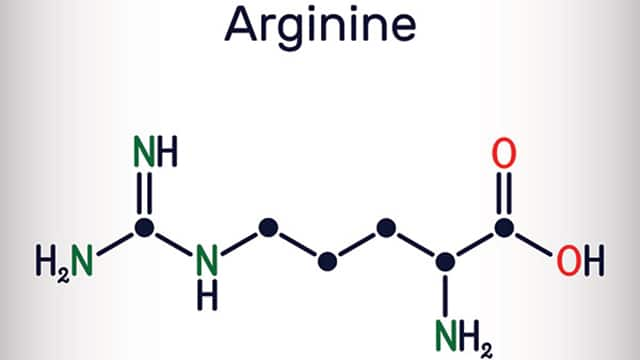

The importance of antibacterial ingredients in oral care for patients with periodontal disease

Read More